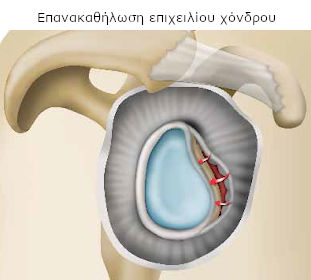

- είτε τη συγκράτηση του σάκου που περιβάλλει την άρθρωση (θύλακος) ή/και του επιχειλίου χόνδρου και την επανακαθήλωσή τους στην αρχικής του θέση, όσο είναι δυνατό. Είναι η τεχνική που παρουσιάζεται εδώ και φέρει το όνομα «Bankart».

Ο χειρουργός σας συγκρατεί και επανατοποθετεί το σάκο που περιβάλλει την άρθρωση (θύλακος) ή/και τον επιχειλίο χόνδρο. Στη συνέχεια προχωρεί στη συρραφή, με μέθοδο της επιλογής του.

Μπορεί επίσης να προβεί και σε επιπλέον ενέργειες αποκατάστασης, ανάλογα με τις βλάβες που διαπιστώνει.

Ο χειρουργός αποσπά το θύλακο που περιβάλλει την άρθρωση και ανάλογα με τις βλάβες που διαπιστώνει, διατήρει το μέρος εκείνο που προσεγγίζει τη φυσιολογική του μορφή. Μόλις τον επανατοποθετήσει στη θέση του, προχωρεί στη συρραφή για να τον σταθεροποιήσει στην κεφαλή του βραχίονιου.

Υπάρχουν διάφορες μέθοδοι συρραφής (βίδες, ράμματα, άγκυρες κτλ). Τα υλικά που χρησιμοποιούνται, συνήθως δεν αφαιρούνται, καθώς είναι πολύ μικρά ή απορροφούνται από τον οργανισμό (απορροφήσιμο υλικό).